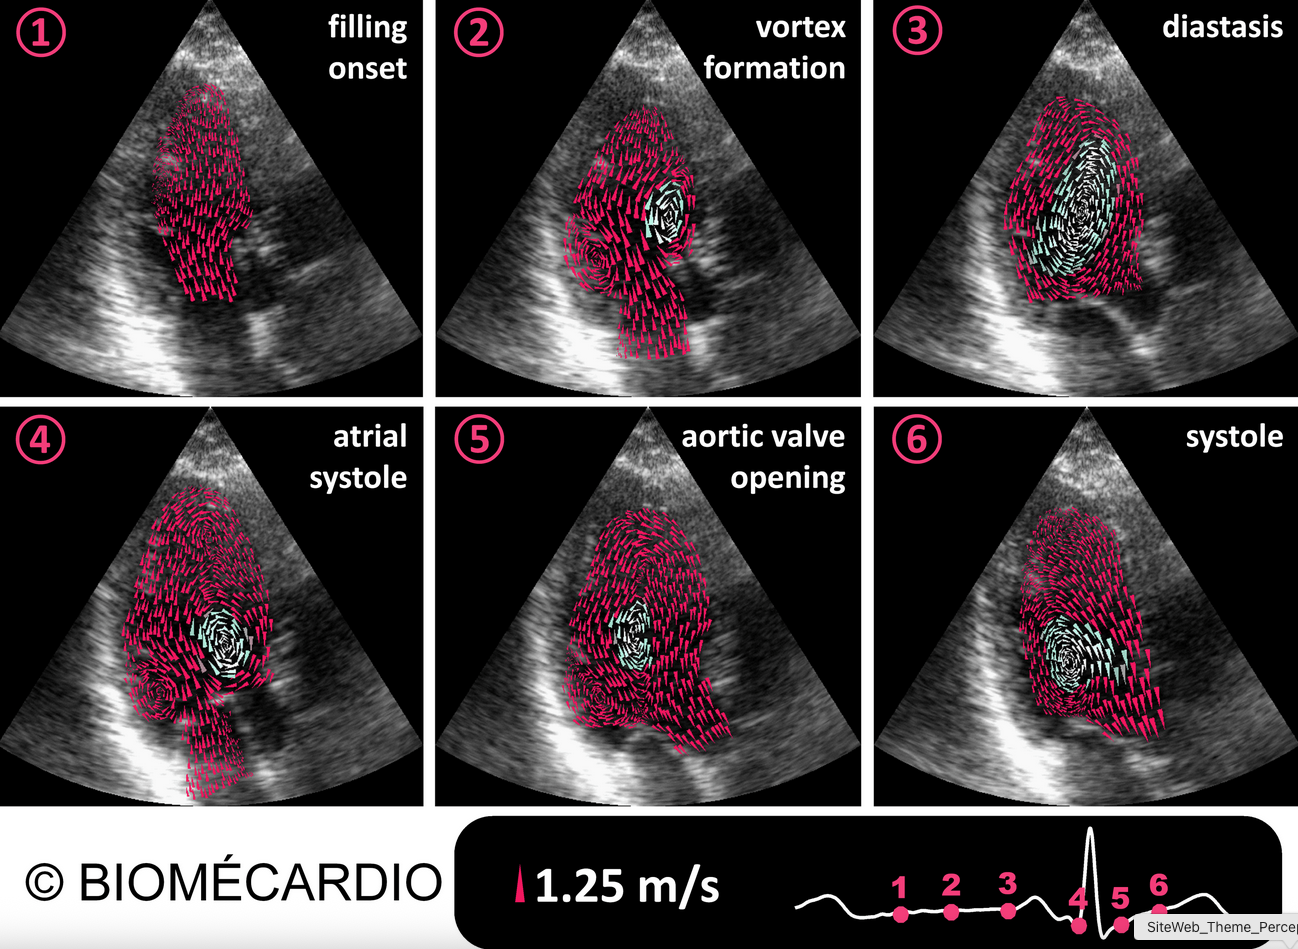

Intraventricular vector flow mapping (iVFM): from standard methods to AI and clinical translation

Abstract: We will cover the evolution of intraventricular Vector Flow Mapping (iVFM) for echocardiography, a technique for intracardiac flow vectors from standard color Doppler images. We will begin with the original physics-based 2D method and its progression to 3D flow analysis. The focus will then shift to the integration of artificial intelligence, accelerating its path into clinical software for improved assessment of cardiac function.